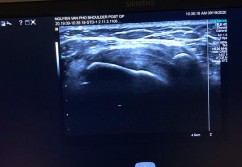

Hình phụ lục 2D: Hình ảnh liền gân độ 1 trên Siêu Âm và độ 2 trên CHT khi khâu phục hồi tổn thương ở tháng thứ 7 sau mổ

(Nguồn: BN nghiên cứu)